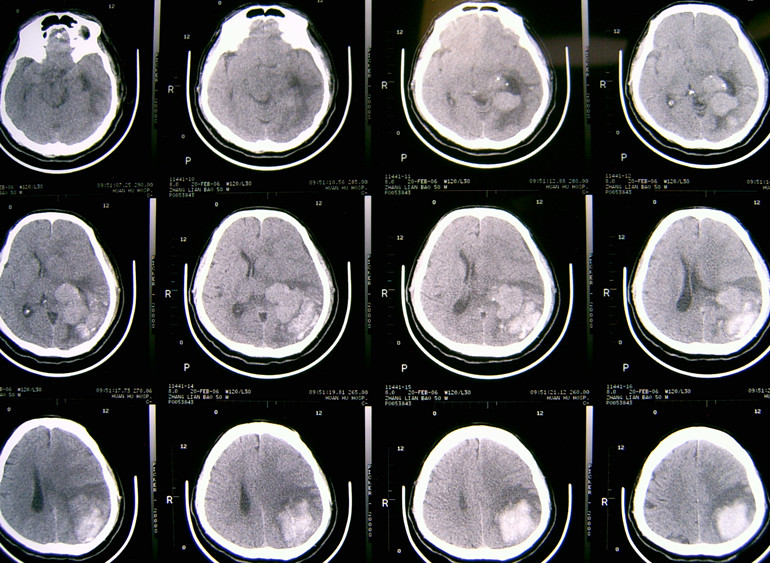

(1)注意识别脑瘤卒中的平扫CT及 MIR片特点:①多为形态不规则密度不均匀的混杂密度病灶,而高血压脑出血多为密度较均匀的类圆形团块状较高密度灶;② 病灶常位于远离中线的脑叶,而高血压脑出血的病灶常位于基底节区及丘脑区;③ 其病灶相对于高血压脑出血病灶的周围水肿比较明显,出血灶周围常有较广泛的大片脑水肿低密度区,而一般脑血肿周围常仅有薄的水肿带;见影像片1,2

影像片1:CT平扫,示形态不规则密度不均匀的混杂密度病灶,位于枕叶及侧脑室枕角处,局部水肿明显。